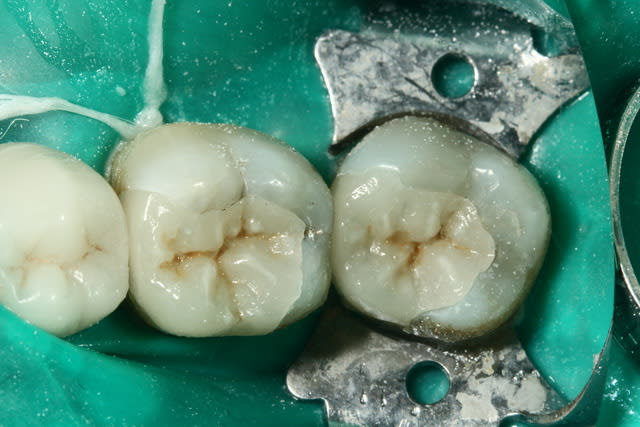

dis moi, alapex, y a pas une carie occlusale sur la 47? çà m'a l'air douteux...